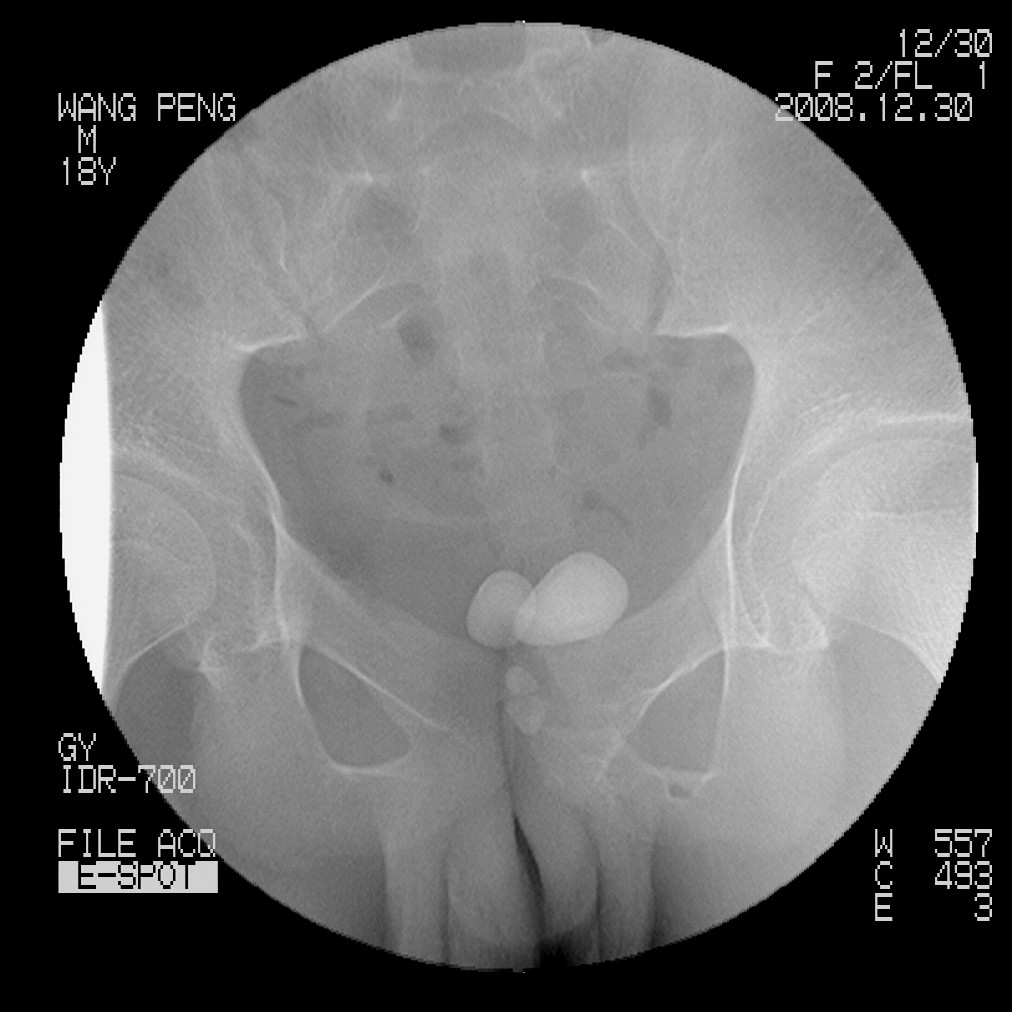

标题: X6910:经典的膀胱及尿道多发结石 [打印本页]

标题: X6910:经典的膀胱及尿道多发结石

患者,男,18岁,尿流不畅数月。

膀胱及后尿道多发结石,谢楼主分享

膀胱及尿道多发结石。

膀胱及后尿道多发结石,谢谢分享---------------------------

膀胱及后尿道多发结石